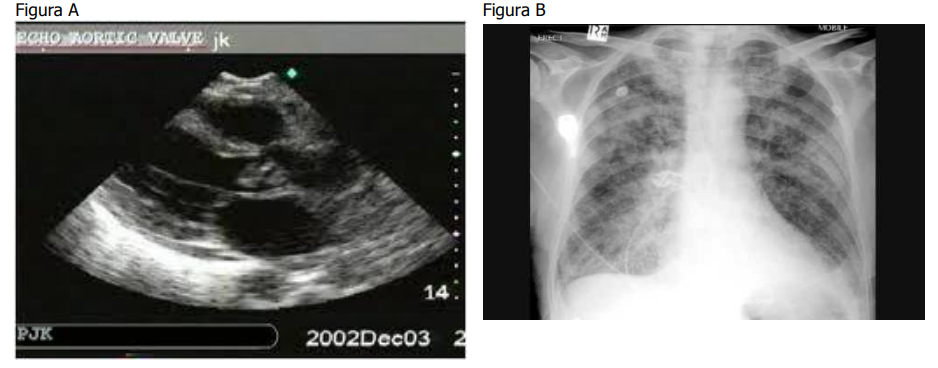

Paciente de 30 anos consulta na emergência com história de febre há quinze dias e início de dispneia há quatro dias. No exame físico, apresenta PA de 90/60 mmHg e FC de 110 bpm. A ausculta cardíaca apresenta sopro diastólico. O ecocardiograma transtorácico e o RX de tórax estão representados nas figuras A e B, respectivamente.

Qual o melhor manejo frente a esse caso?